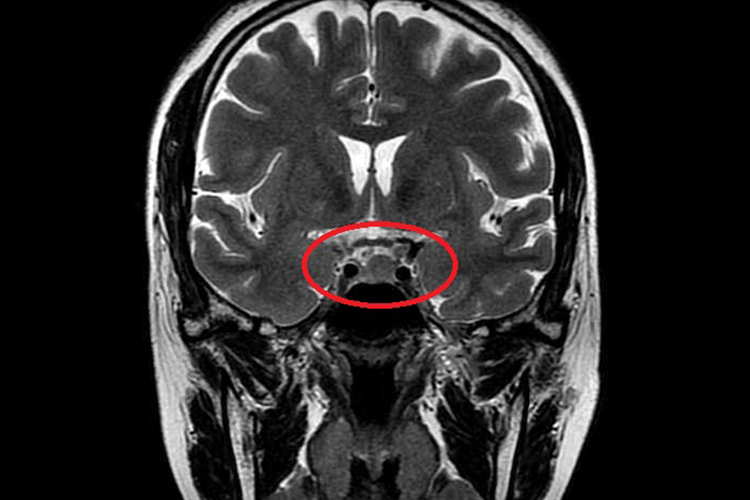

- 经蝶手术:临床上较为常用的手术方式,属于微创治疗,通过蝶窦组织将微腺瘤进行切除,有时仅切除增生垂体组织,术后大部分患者垂体前叶功能可得到恢复。